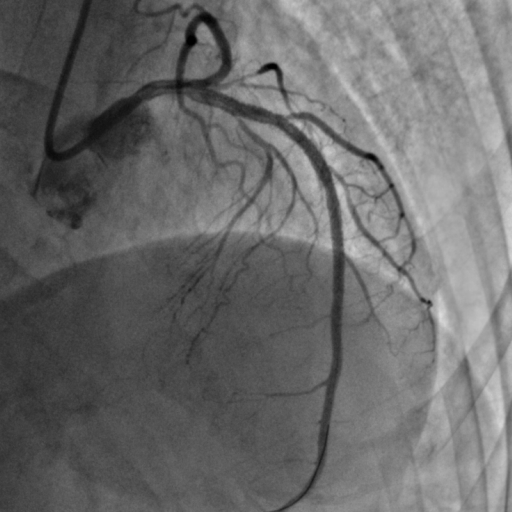

李怡教授使用该系统成功指导了一例前降支次全闭塞病例的PCI治疗。术中李怡教授通过IVUS细致地观察了患者前降支的近中段病变部位,在高清图像下对病变部位的管腔面积与斑块负荷等信息作出了详细的分析,并在成功为患者植入支架后,进一步对支架的植入效果进行了全面的评估及优化。李怡教授表示60MHzIVUS导管所生成的高清图像及管腔智能识别技术的辅助,给手术医生创造了更高效的读图分析环境,其功能的精准程度超出预期,令人印象深刻。

术前

术后